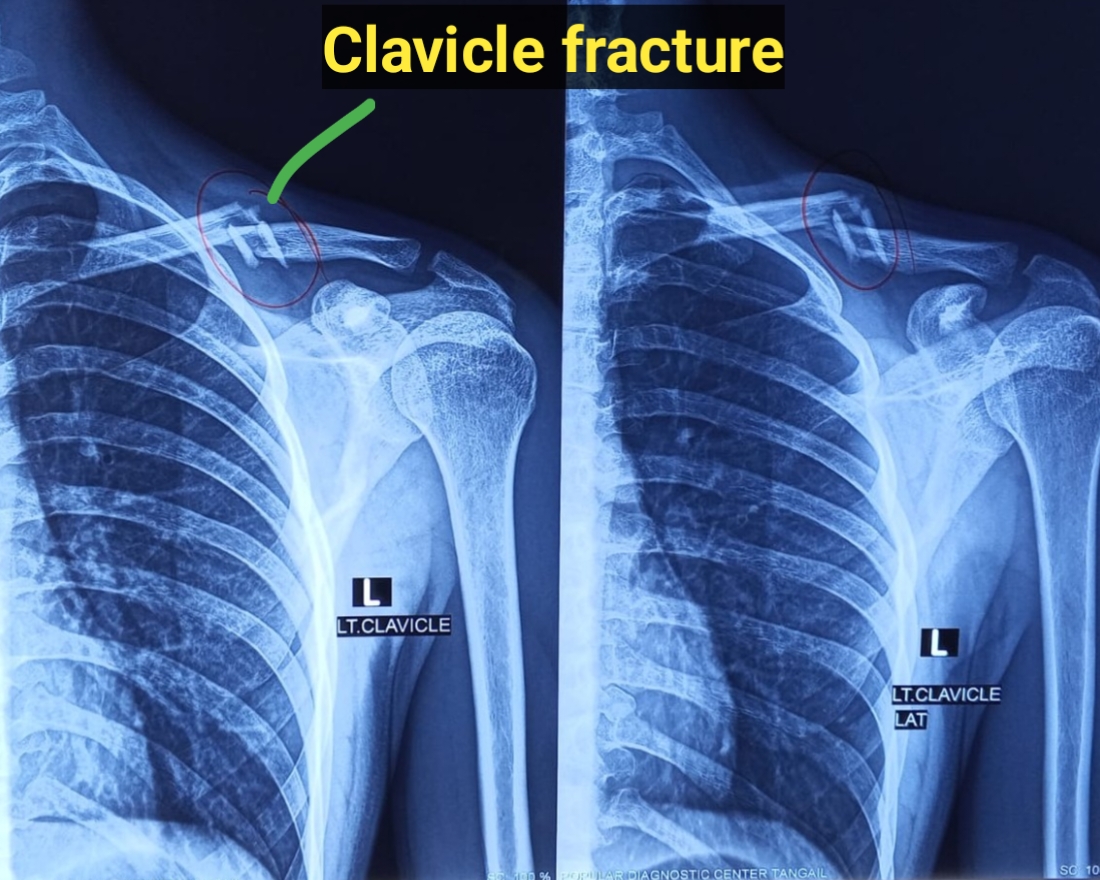

মাথা ব্যথা, ঘাড় ব্যথা, কোমর ব্যথা, পিএলআইডি সমস্যা, হেড ইনজুরি , স্পাইন ইনজুরি , স্পাইনের রড-স্ক্র ফিক্সেশন, মস্তিষ্ক - স্নায়ু - মেরুদণ্ড ব্যথা, স্পাইনাল টিউমার, ব্রেইন টিউমার, প্যারালাইসিস বা পক্ষাঘাত, স্ট্রোক, হাত - পায়ে ব্যথা, হাতে পায়ে ঝিমঝিম ভাব , শিশু নিউরোসার্জারি , ভাসকুলার নিউরোসার্জারি বিশেষজ্ঞ ও নিউরোসার্জন।